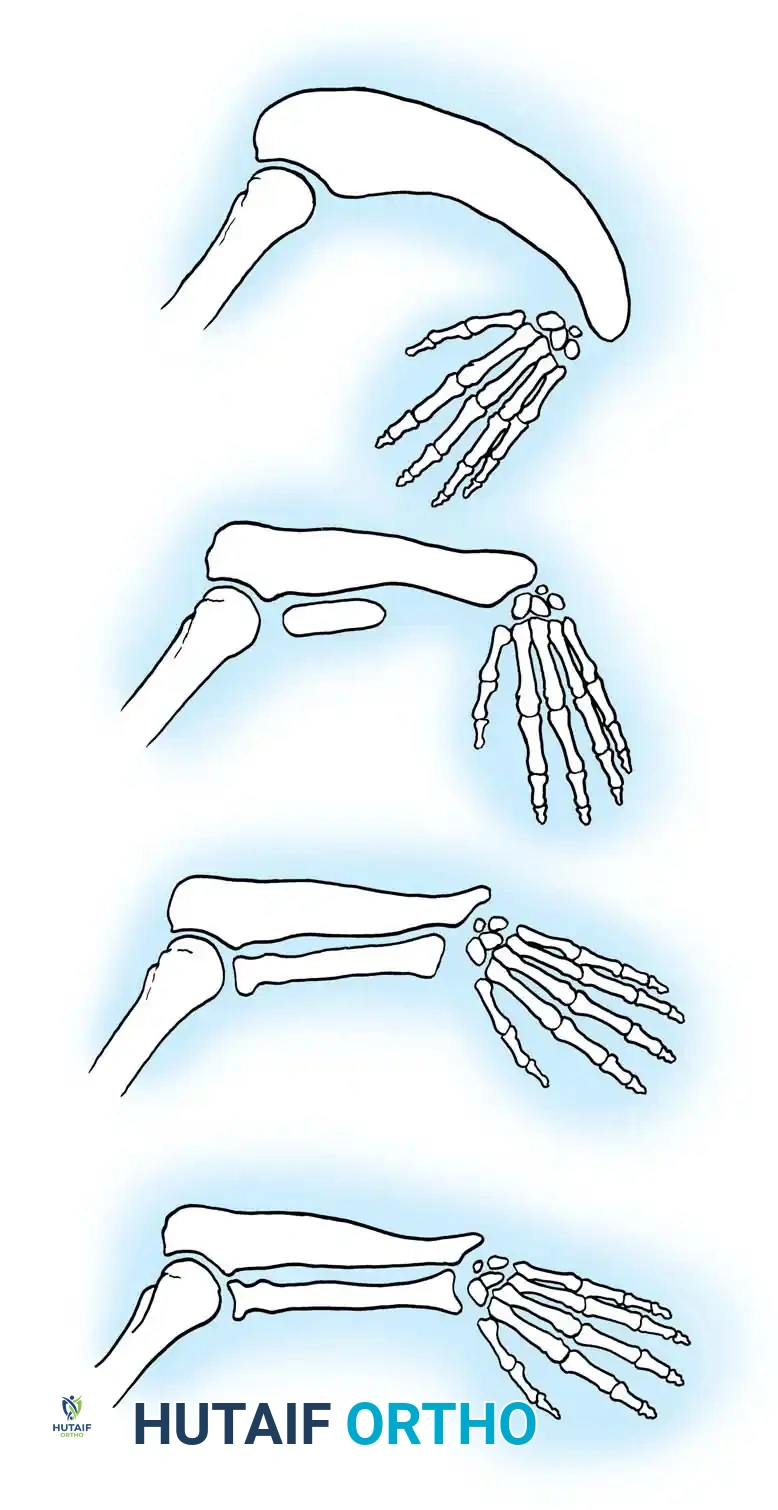

Growth and differentiation proceed in a strict proximal-to-distal fashion, governed by three primary signaling centers that dictate the three-dimensional spatial orientation of the limb:

- The Apical Ectodermal Ridge (AER): Located at the distal tip of the limb bud, the AER is responsible for proximal-to-distal growth. It secretes Fibroblast Growth Factors (FGFs) that maintain the underlying mesoderm in a highly proliferative state known as the progress zone.

- The Zone of Polarizing Activity (ZPA): Situated in the posterior (postaxial) margin of the limb bud mesoderm, the ZPA controls radioulnar (anterior-posterior) differentiation. The primary morphogen secreted by the ZPA is the Sonic Hedgehog (SHH) protein. Disruptions in SHH signaling explain the clinical phenomenon where ulnar-deficient limbs frequently present with associated preaxial (radial) hand deficiencies.

- The Wingless-Type (WNT) Signaling Center: Located within the dorsal ectoderm, this center secretes WNT-7a, which induces the expression of LMX1B in the underlying mesoderm, thereby determining the dorsal differentiation of the limb.

Fig. 76-1 Limb bud. The apical ectodermal ridge extends from anterior to posterior along the dorsal/ventral boundary of the growing limb bud. Proximal to the AER is the progress zone. Within the posterior mesoderm is the zone of polarizing activity. These centers are highly interconnected; limb patterning and growth depend entirely on their coordinated function.